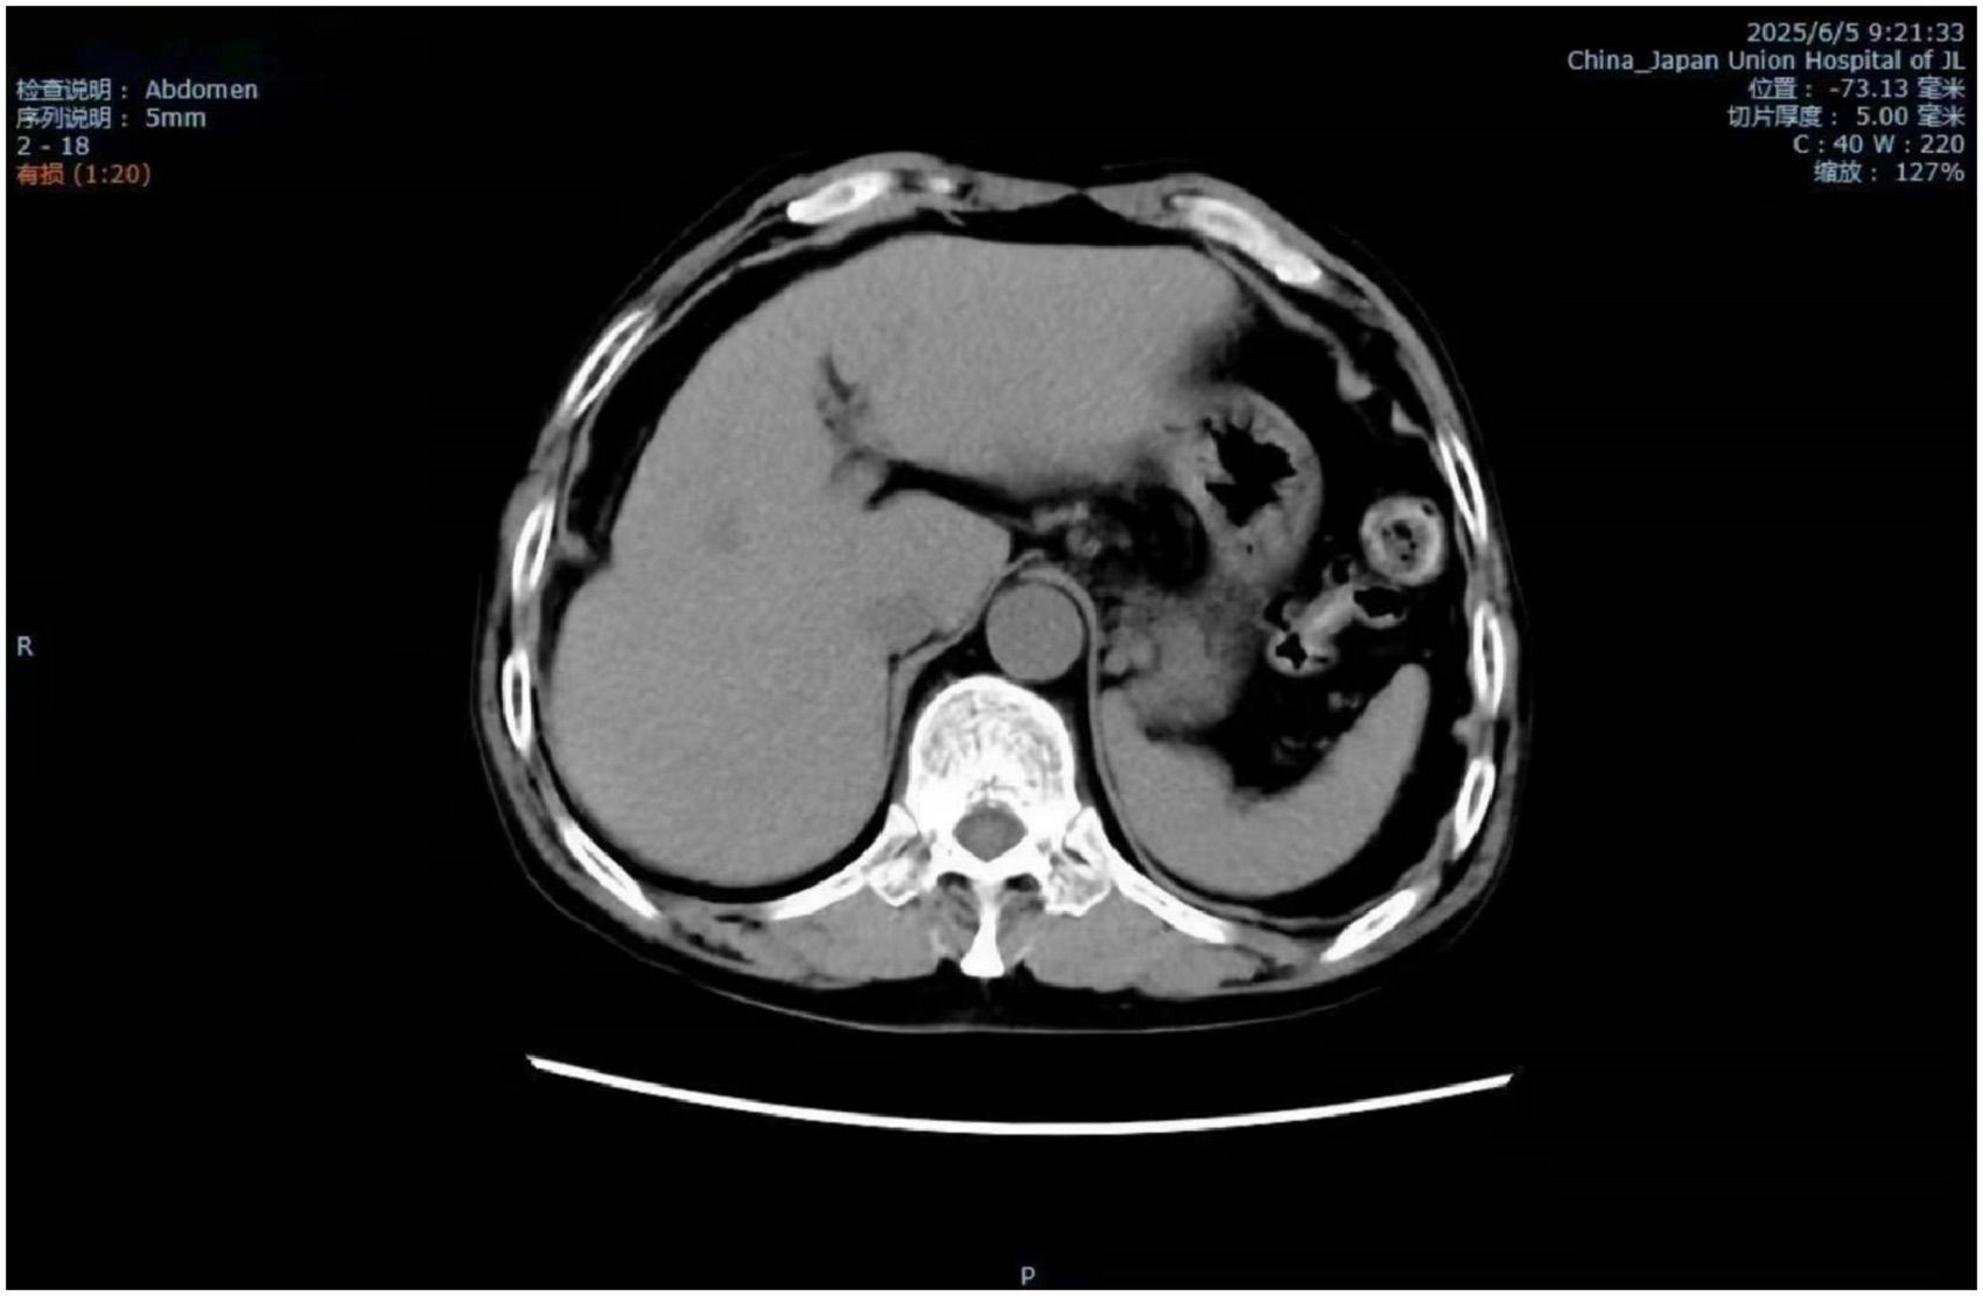

Background Madelung's disease (MD) is a rare disorder of fat metabolism, with symptoms often characterized by the appearance of chronic accumulations of abnormal adipose tissue in areas such as the neck and neckline, upper back and chest. Nowadays, its pathogenesis is still unknown, and some scholars have suggested that its etiology is closely related to alcohol consumption, and that it is associated with a variety of metabolic diseases such as liver disease, hypertension, diabetes mellitus, dyslipidemia, and peripheral neurological damage. Currently, there are very few reported cases of Madelung's disease complicated by alcoholic liver disease and liver cirrhosis (LC), making this case worthy of reporting. Case summaries This article reports on a 60-year-old man, the main point of view"The patient has experienced edema in both lower limbs for two weeks , accompanied by a long history of alcohol consumption".Clinical examination showed subcutaneous swelling of the neck, which has been clearly present for three years. The diagnosis of Madelung's disease combined with alcoholic liver disease and liver cirrhosis was made based on laboratory tests of liver function, ultrasound of the neck vessels, ultrasound of the superficial tissues of the neck, and CT of the abdomen. The patient has not exhibited restricted neck mobility or symptoms of tracheoesophageal fat syndrome, which affects swallowing and breathing, and refused neck surgery treatment and received hepatoprotective therapy and traditional agents. After 14 days and two cycles of Chinese medicine,edema subsided, and the size of the subcutaneous mass remained stable. Result Madelung's disease is often underdiagnosed and misdiagnosed because of its low prevalence. The purpose of this article is to illustrate the need to be vigilant in clinical encounters with patients with Madelung's disease combined with alcoholic liver disease and liver cirrhosis, to achieve early intervention and treatment, and to prevent complications. The etiology of this disease remains unclear. Further research into its pathophysiological mechanisms should be pursued, opening new avenues for therapeutic investigations.